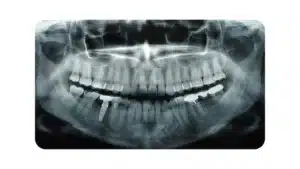

When your child reaches a certain age, we will verify whether their teeth are developing regularly and in the proper sequence. In order to aid in this evaluation, we will take a panorex x-ray, which is a two-dimensional image that displays the head and neck’s inner architecture from the nose to the chin and all the way back to the TMJ.

In addition, wisdom teeth, which might be difficult to detect with other forms of x-rays, are far easier to inspect with panorex images. In addition, these photographs will reveal any bone fractures, malignancies, sinus infections, or cysts that may be present.